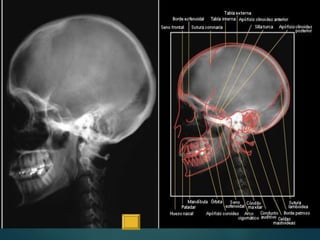

Este documento proporciona instrucciones para realizar diferentes proyecciones radiográficas del cráneo, incluyendo las proyecciones anteroposterior (AP), submentovertex (SMV), parietoorbitaria y transorbitaria de Guillen. Describe los ángulos y posiciones requeridos para cada proyección y las estructuras óseas que deberían ser visibles en cada imagen resultante.